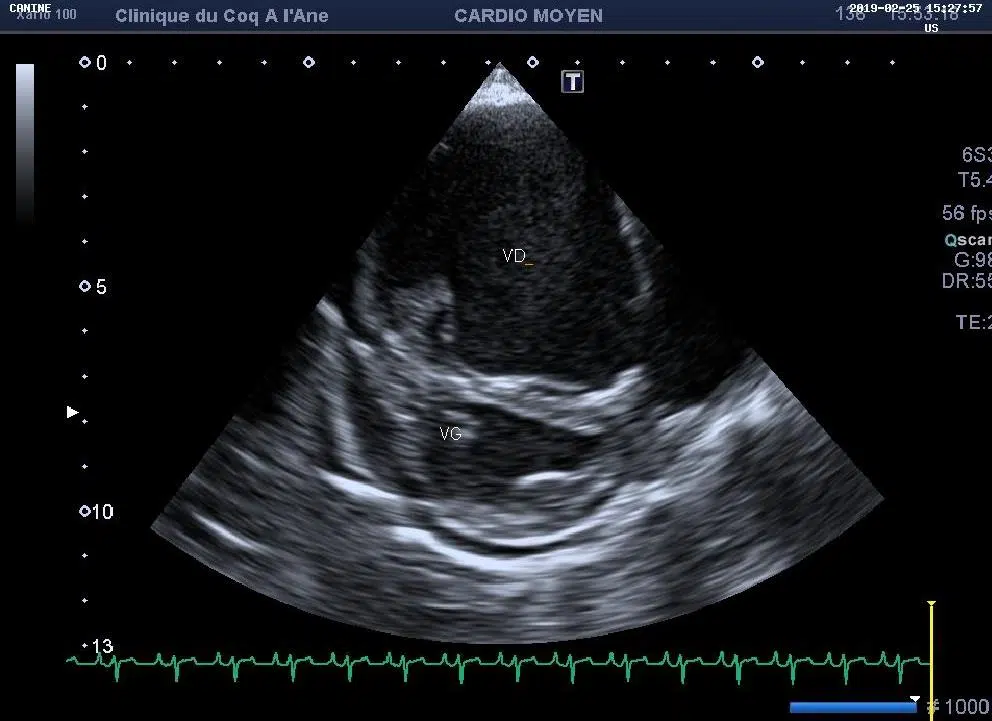

• 2 échographes dédiés aux petits animaux munis respectivement de 2 et 4 sondes